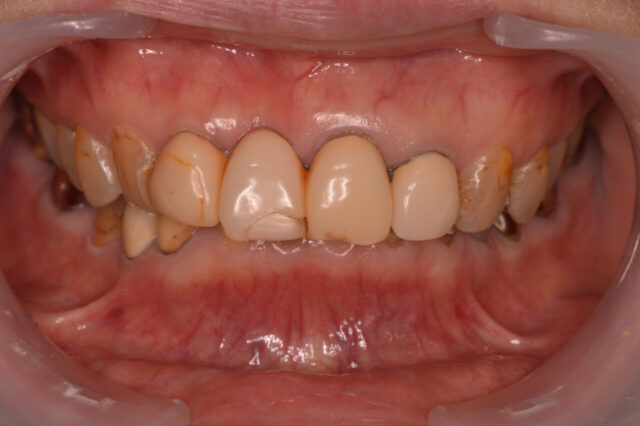

前歯のすきっ歯(正中離開)を1日で改善|ダイレクトボンディング症例

before

after

性別 女性 主訴 前歯のすきっ歯(正中離開)が気になる/姪浜周辺で短期間で治したい 治療 処置内容

マイクロスコープ下での精密診断

ラバーダム防湿

歯面処理(エッチング・ボンディング)

高強度コンポジットレジンによる築盛

形態・左右対称性の調整

咬合調整および最終研磨料金 1本100,000+tax 備考 歯をほとんど削らずに治療可能

即日で審美的改善が可能

将来的な修正が比較的容易

ケースによっては矯正治療が適応となる場合あり

経年的な変色・摩耗の可能性あり(定期的なメンテナンスを推奨)